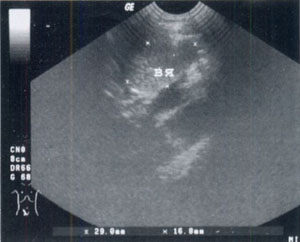

Глава 3. Лапароскопические операции при брюшном крипторхизме у взрослых | UroWeb.ru Урологический информационный портал